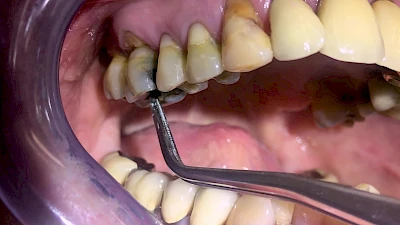

Eine geringe spürbare Beweglichkeit der Zähne ist durchaus normal, da Zähne über Fasern im Kieferknochen aufgehängt sind. Lassen sich Zähne, Kronen oder Brücken jedoch deutlich sichtbar bewegen, besteht die Gefahr, dass sie sich lösen und verschluckt oder aspiriert werden. Deshalb sollte in diesen Fällen der Zahnarzt verständigt werden.